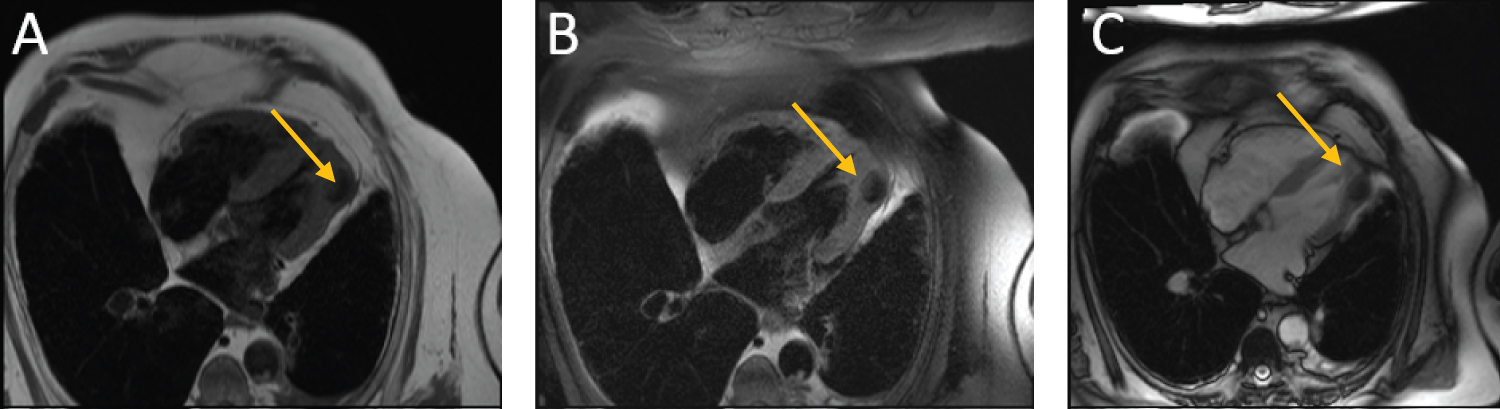

This study reported a 3 cm mass in the mid and distal anterolateral wall of the left ventricle (Figure 1). Aside from the patients preexisting well-compensated chronic diastolic heart failure, the mass was felt to be clinically asymptomatic. Physical exam findings showed a well appearing patient in no acute distress. There was no jugular venous distention and cardiac auscultation demonstrated a regular rate and rhythm without murmurs or gallops. Pulmonary exam revealed diffusely decreased breath sounds with no obvious rales or rhonchi. Radial and pedal pulses were palpable bilaterally. There was no peripheral edema.

Figure 1: Staging CT for patient's known squamous cell carcinoma. A) Noncontrast and B) contrast enhanced CT chest showing mass in the mid to distal anterolateral wall of left ventricle. View Figure 1